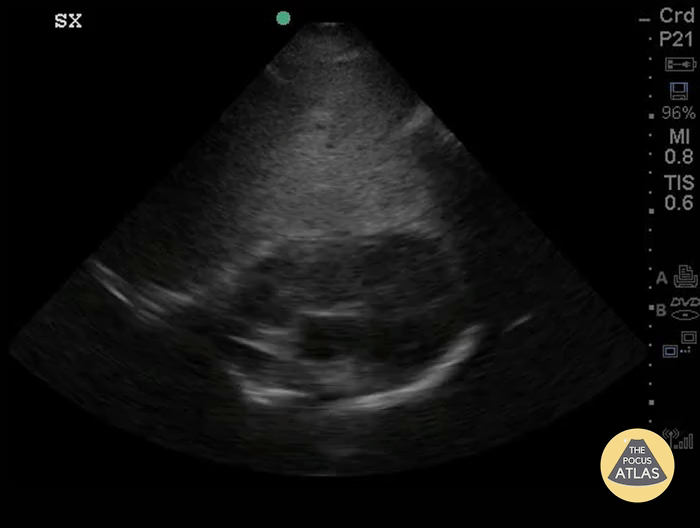

Extensive tumor-thrombus complex originating from a right adrenal malignancy that invaded the IVC and migrated cephalad until it was prolapsing through the tricuspid valve into the RV. Shockingly, this monstrous goomba was almost invisible on PSL, PSS, and A4C views. Submitted by Dr. Elias Jaffa